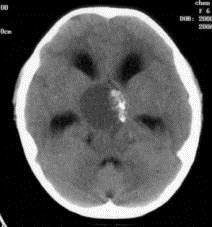

问题 病历摘要:??患者女性,6岁,半年来感觉视力模糊,近10天出现反复头痛,间有恶心呕吐,精神转差,查体:神志清楚,身高90cm,体重25Kg,血压90/55mmHg,右眼视力4.6,左眼视力4.8,双侧视乳头水肿,颈软,伸舌居中,四肢肌张力正常,肌力5级,双侧Babinski征(-)。 该患者就诊时,应作那些必要的检查?